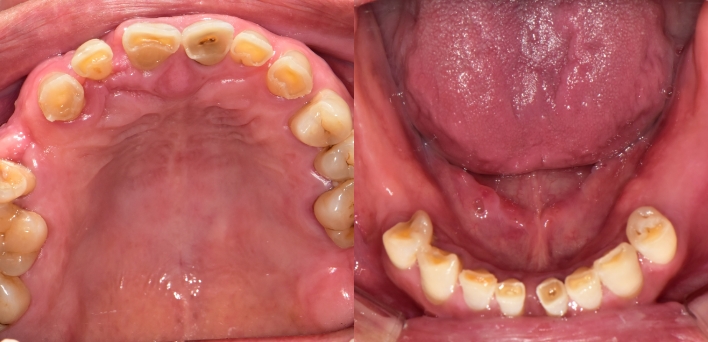

임플란트 : 손 ** 님 (50대)

치아가 있다는게, 아직도 정말 꿈만 같아요.

Before Before

2020.02.30

After After

※ 더서울치과의원은 의료법을 준수하며 위 케이스는 실제 환자의 동의를 얻은 사례로 치료 전, 후가 동일한 환경에서 촬영되었습니다.

환자 케이스에 따라 부작용이 발생할 수 있습니다. 이 부분은 의료진의 충분한 상담과 체크를 통해 예방하고 줄일 수 있습니다.

[임플란트 부작용] 수술 후 관리가 소홀할 경우 출혈, 주위염 등의 부작용이 발생할 수 있어 구강 위생을 철저히 유지하고, 정기적인 검진을 통해 상태를 점검하는 것이 중요합니다.

환자 특징

환자 특징01무치악 상태

환자 특징02수년간 무치악으로 지내심

임플란트가 불가능할것이라

생각하고 내원

위, 아래 6개씩 식립

디지털 풀아치 임플란트